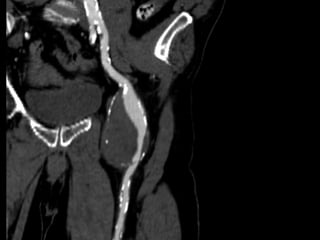

Cas # 1 ♂ 71 ans entrepreneur…  ATCD  PABI ’99  Investigation ‘2011  FCD 35 mm  FPD 30 mm  Popl D 35 mm  Popl G 23 mm  FCG 18 mm

72 59 ATCD: PABI’99 re: AIliaquebil ATCD: Db , ROH Korsakoff, MCASPAC, fempop bilat Anévr popl. Suivi Anévr fém et popl RC: référé rupture…en fait «non» mais symptomatique Quest: … Quest.:C.I. non limitante E.P.: masse puls. > 5cm ing. D non doul et autres… E.P.: masse pulsatile >5 cm ing G doul palpation, nécrose sèche extr dist un orteil non doul Pls périph N Doppler Angioscan: dimensions anévr. ? Angioscan: dimensions Anévr ?

Cas #1 72ans Cas #2 59 ans  Suivi  ATCD  PABI  Particularités  Anévrysme Fémorale profonde  Cutler-Darling type 1  Symptomatique  ATCD  Fem-pop. Bilatéraux…  Particularités  Korsakoff  Cutler-Darling type 2 thrombosés